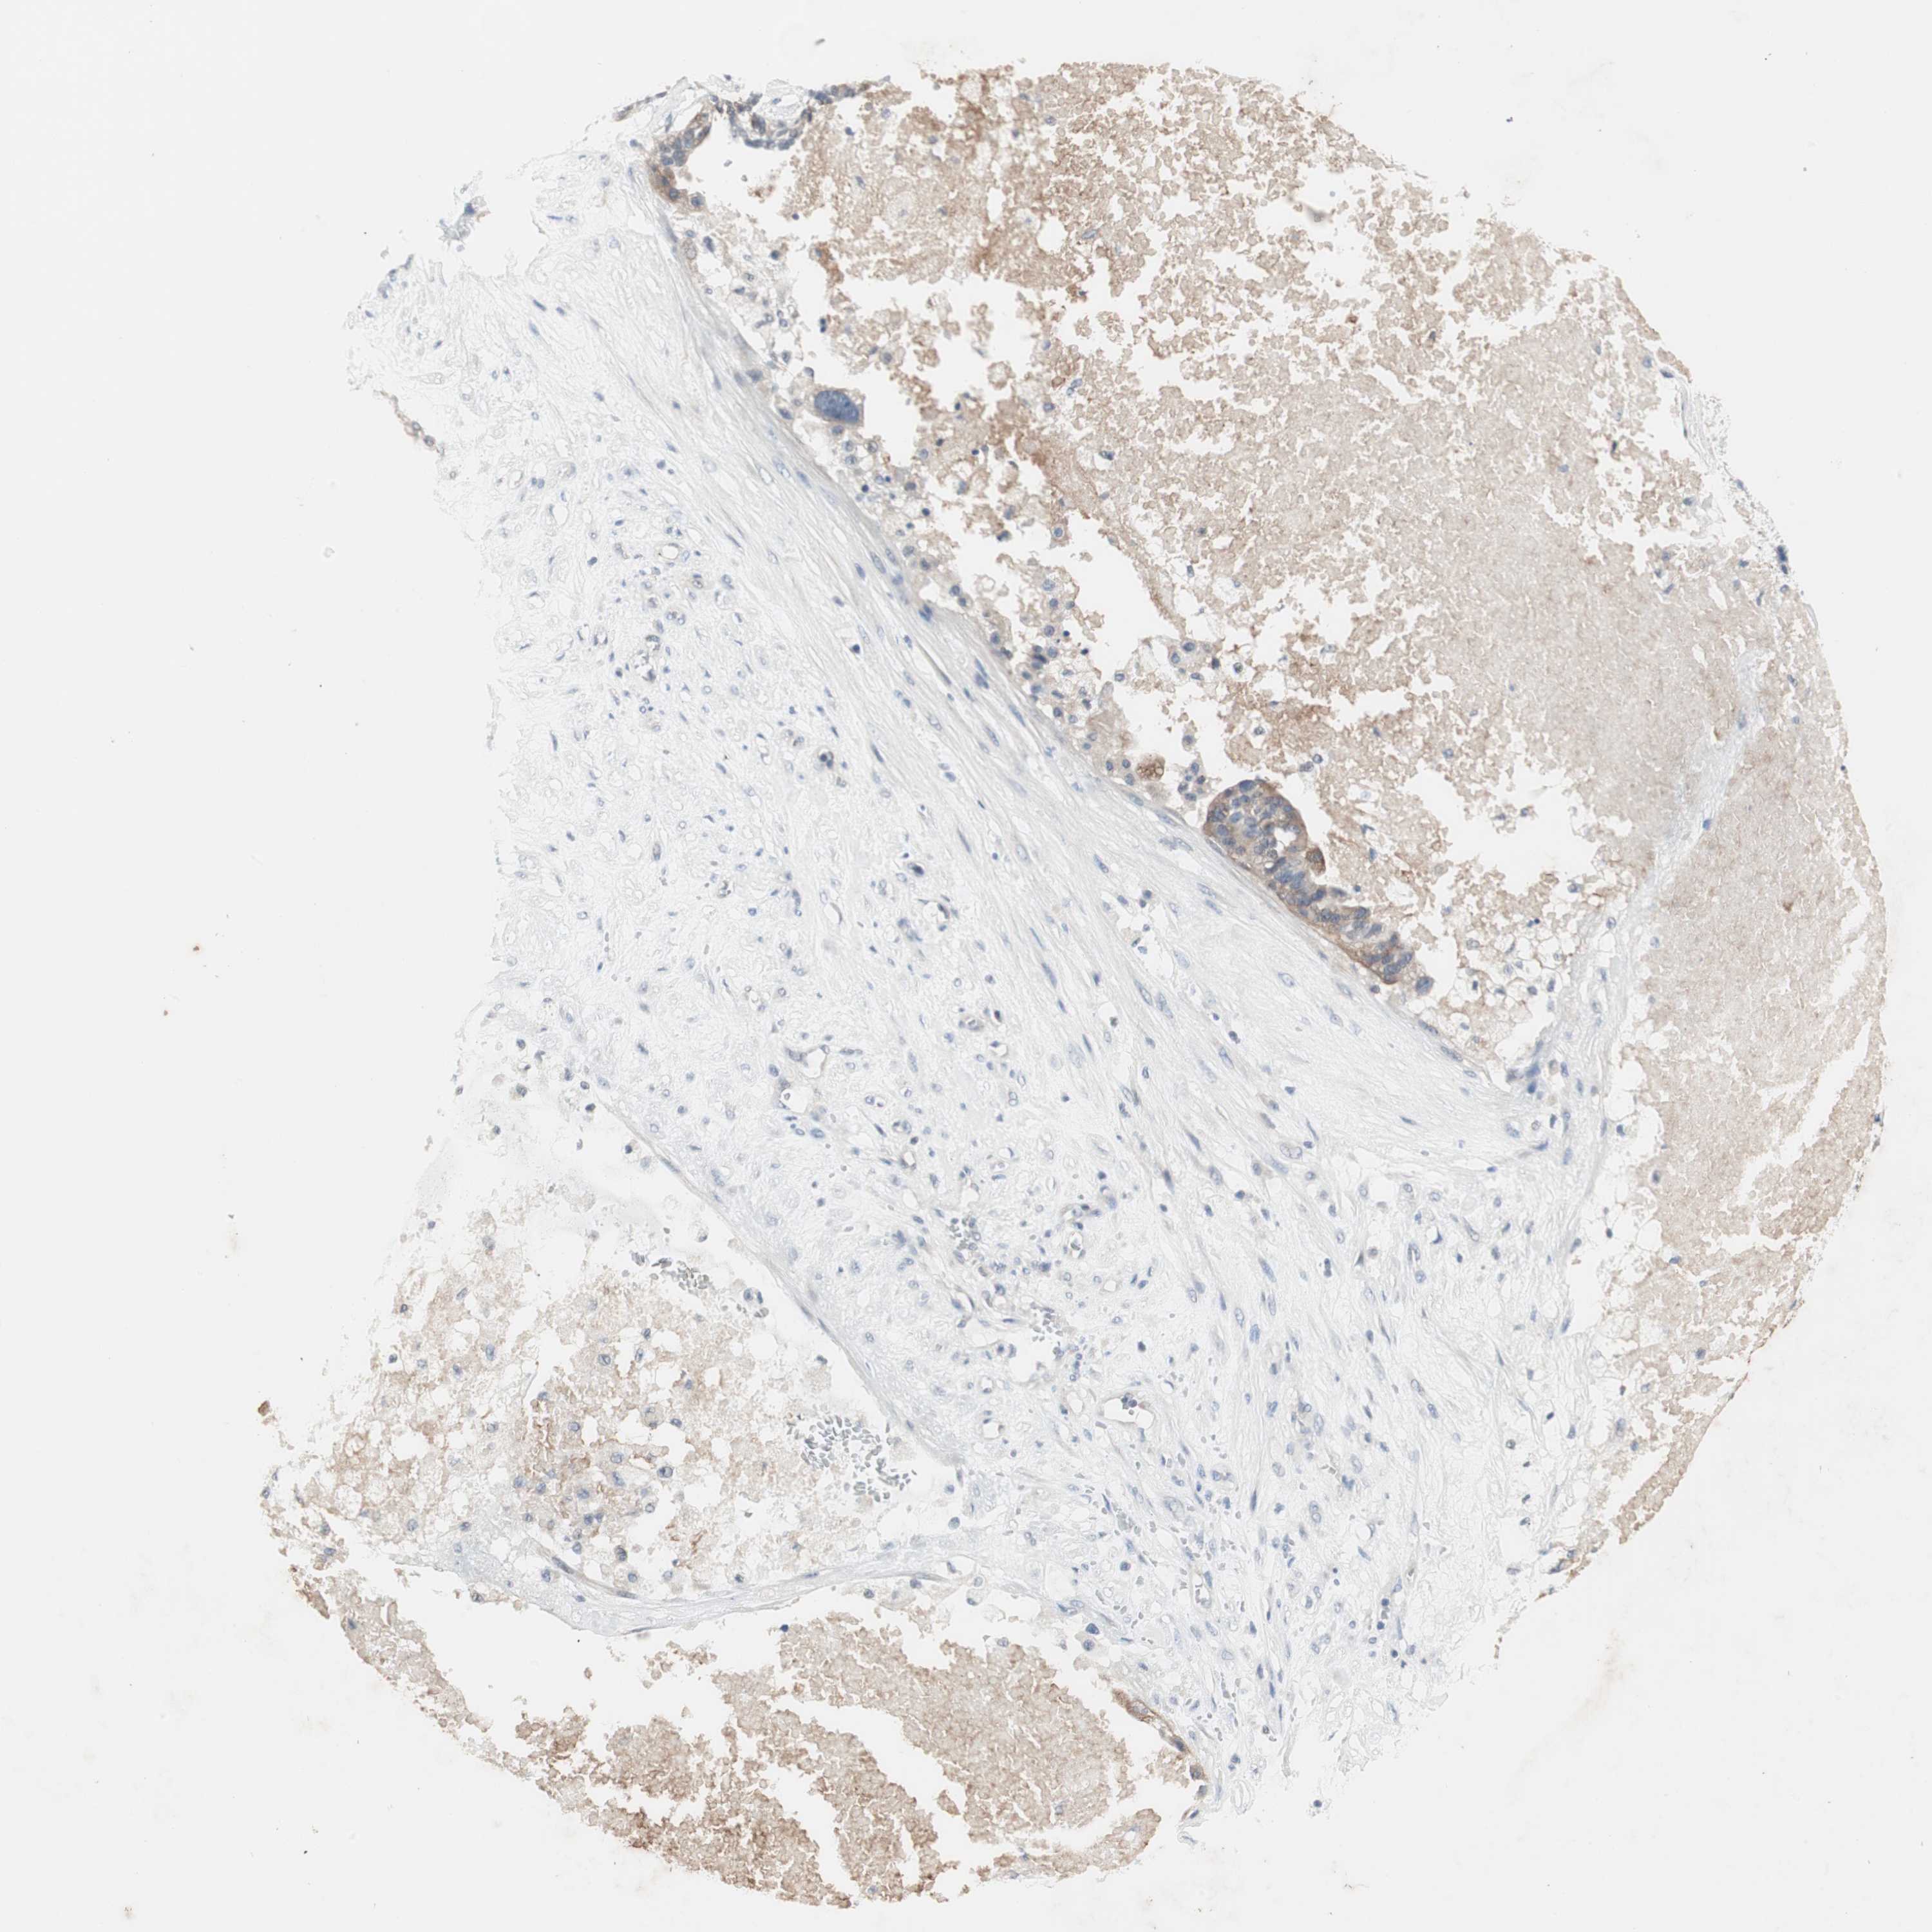

OVARIAN CANCER - Protein expressioni

A mouse-over function shows sample information and annotation data. Click on an image to view it in a full screen mode. Samples can be filtered based on level of antibody staining by selecting one or several of the following categories: high, medium, low and not detected. The assay and annotation is described here.

Note that samples used for immunohistochemistry by the Human Protein Atlas do not correspond to samples in the TCGA dataset.

Antibody stainingi

Antibody staining in the annotated cell types in the current human tissue is reported as not detected, low, medium, or high, based on conventional immunohistochemistry profiling in selected tissues. This score is based on the combination of the staining intensity and fraction of stained cells.

Each image is clickable and will lead to virtual microscopy that enables deeper exploration of all samples and also displays staining intensity scores, fraction scores and subcellular localization as well as patient and tissue information for each sample.

Antibody HPA036348

Antibody HPA036349

Antibody CAB002422

Antibody CAB005258

Cystadenocarcinoma, serous, NOS

Carcinoma, NOS

Cystadenocarcinoma, mucinous, NOS

Carcinoma, endometroid